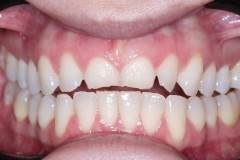

Paciente femenina de 56 años, se presenta a la consulta con puente dental desajustado, con restos alimenticios impactados, se decide realizar un corte de la estructura metálica-porcelana, para conservar piezas restauradas adyacentes, y se coloca un implante dental Marca SIN Implant, realizando provisional para carga inmediata, se espera el proceso de Osteointegración de 4 meses, se observa perfil de emergencia gingival apto, y se procede con la colocación de la corona en Zirconio.